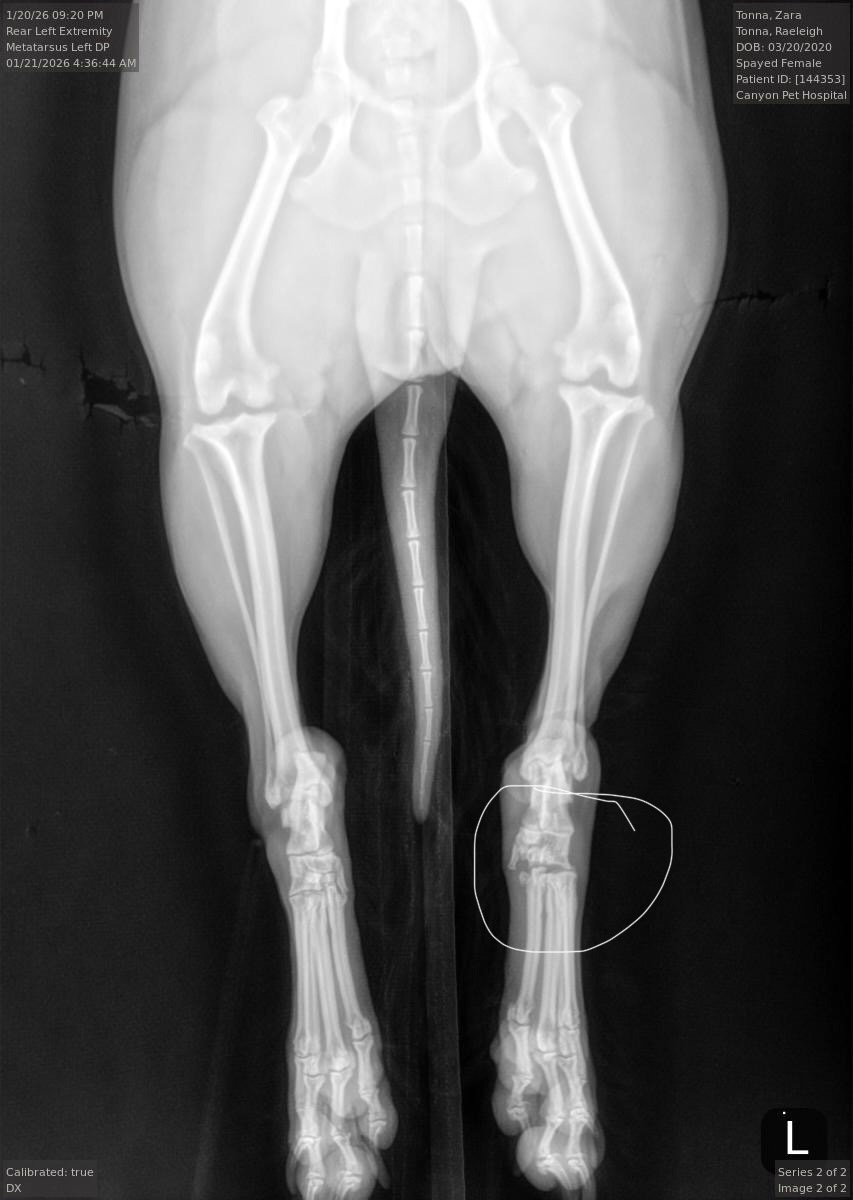

Recently, Zara suffered a devastating freak accident. She experienced a severe joint dislocation in her hind leg where her ankle became separated from her toes. We are now faced with an impossible decision: attempting a surgical fusion or amputating her leg.

We tried to make a home fusion work through splinting, but it has already caused soo many complications. After consulting with several veterinarians, fusion is currently the best long-term option, though we are still waiting on additional trusted opinions. No matter which route we choose, the costs are overwhelming.